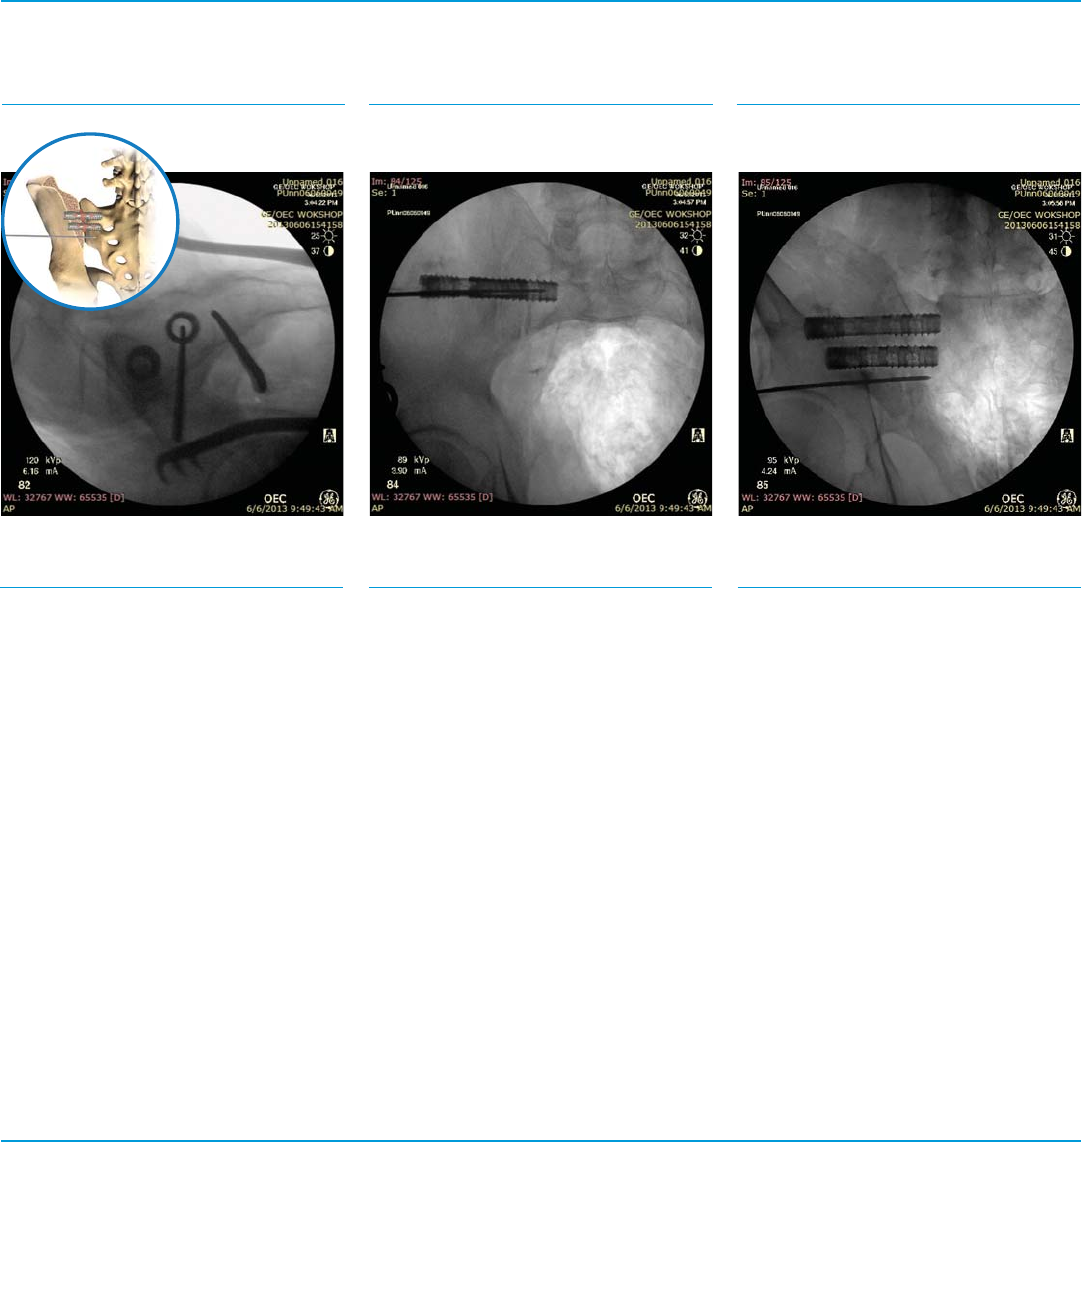

Fig. 17a SFig. 17b SFig. 17c S

Third Implant Targeting

Step 17

Repeat Step 3 for targeting of the third

implant.

Lateral View (Fig. 17a)

Inlet View (Fig. 17b) Outlet View (Fig. 17c)

Fig. 18a SFig. 18b SFig. 18c S

Third Implant Insertion

Step 18

Repeat Steps 4-14.

Lateral View (Fig. 18a)

Inlet View (Fig. 18b) Outlet View (Fig. 18c)

Fig. 19a SFig. 19b SFig. 19c S

Final Implant Construct

Step 19

Confirm final implant placement using Lateral,

Inlet and Outlet views under fluoroscopy.

Lateral View (Fig. 19a)

Inlet View (Fig. 19b) Outlet View (Fig. 19c)